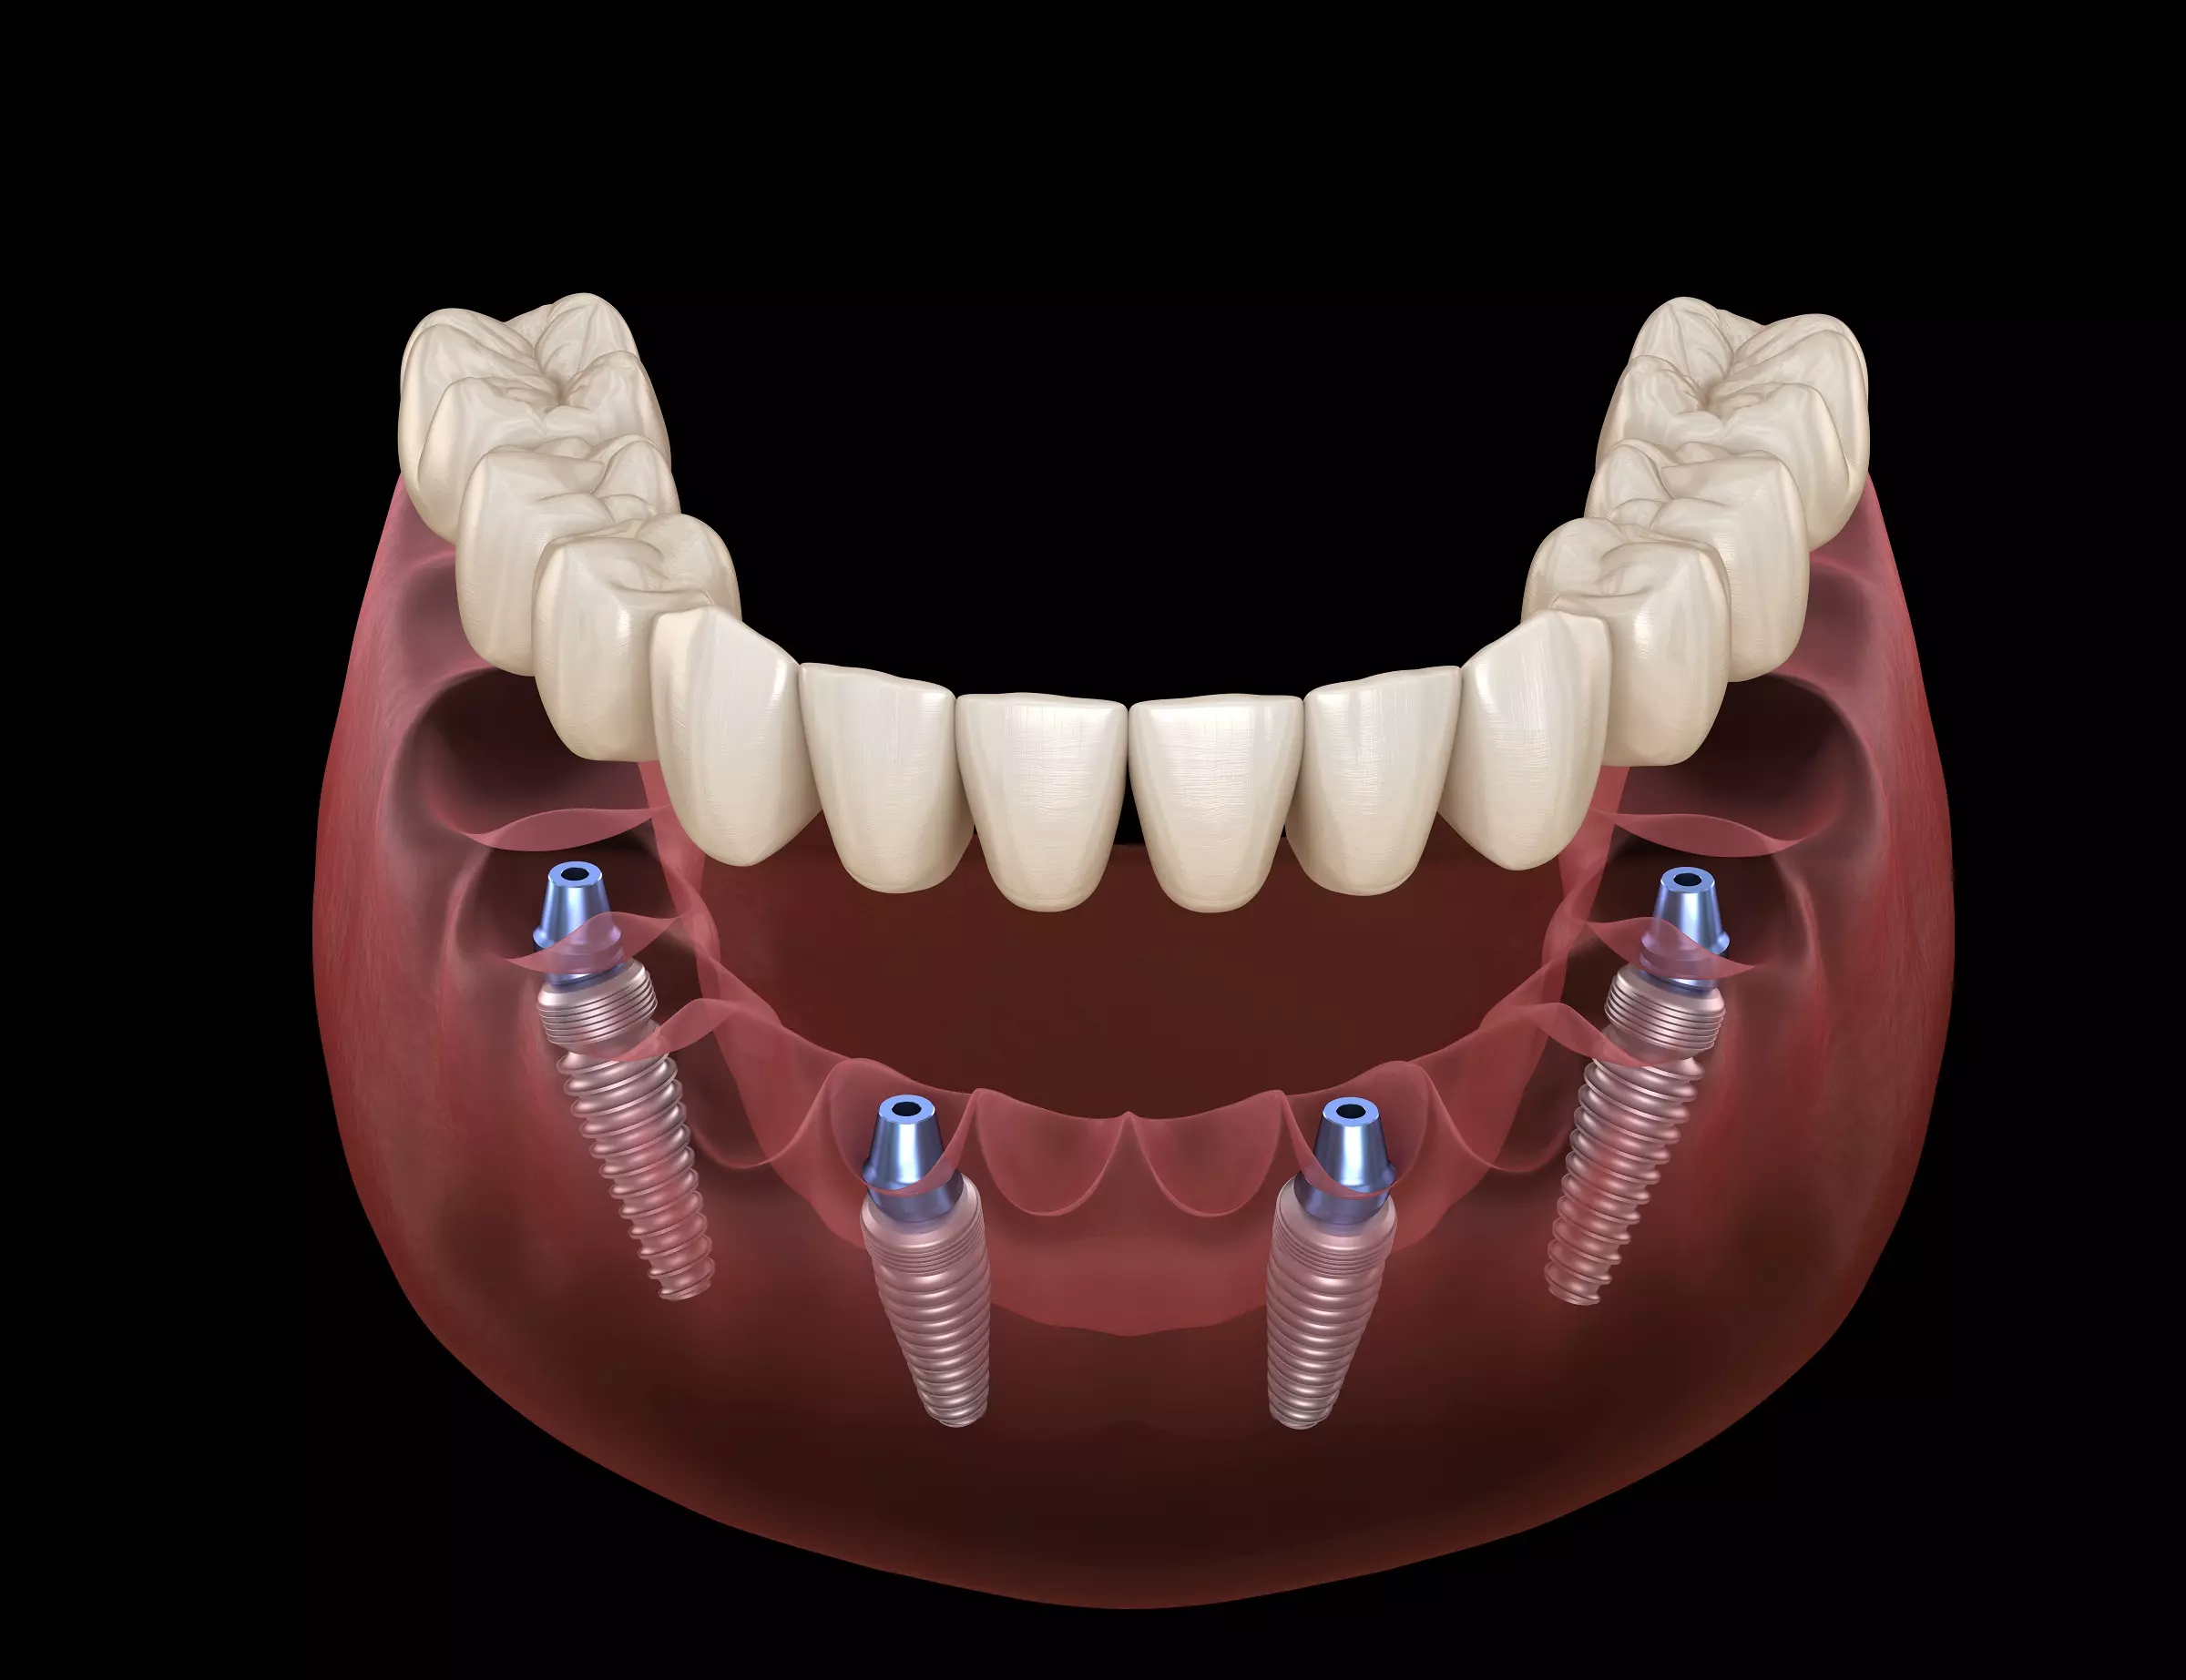

What are All-on-4 Dental Implants?

All-on-4 dental implants are an innovative solution for those who have lost most or all their teeth. The procedure involves placing four dental implants in the jawbone and attaching a complete set of fixed prosthetic teeth to them, creating a stable and natural-looking smile.

The All-on-4 procedure involves the placement of four dental implants strategically positioned in the jawbone. This technique uses the available bone more efficiently and often avoids bone grafting. Once the implants are placed, a complete set of prosthetic teeth are attached, restoring your smile and ability to eat and speak confidently.

- Same-day smile improvement – a temporary teeth restoration is attached to the dental implants within the same day, offering instant smile improvement.

- Permanent missing teeth solution – unlike dentures, the tooth restoration is permanently fixed with an all-on-4 or all-on-6 implant treatment.

- Prevention of bone deterioration – tooth loss can lead to bone loss if the problem is not addressed early enough. All-on-4 or All-on-6 implants replace the function of lost tooth roots, providing continuous stimulation to the jawbone to protect it from deteriorating after teeth extraction.

- Improves comfort – teeth replacement for the entire jaw is secured in place, so it will not rub painfully against the gums the way removable dentures tend to do.

- Restores healthy function – the treatment feels and works like natural teeth, making it easier to speak, bite, and comfortably chew on food.